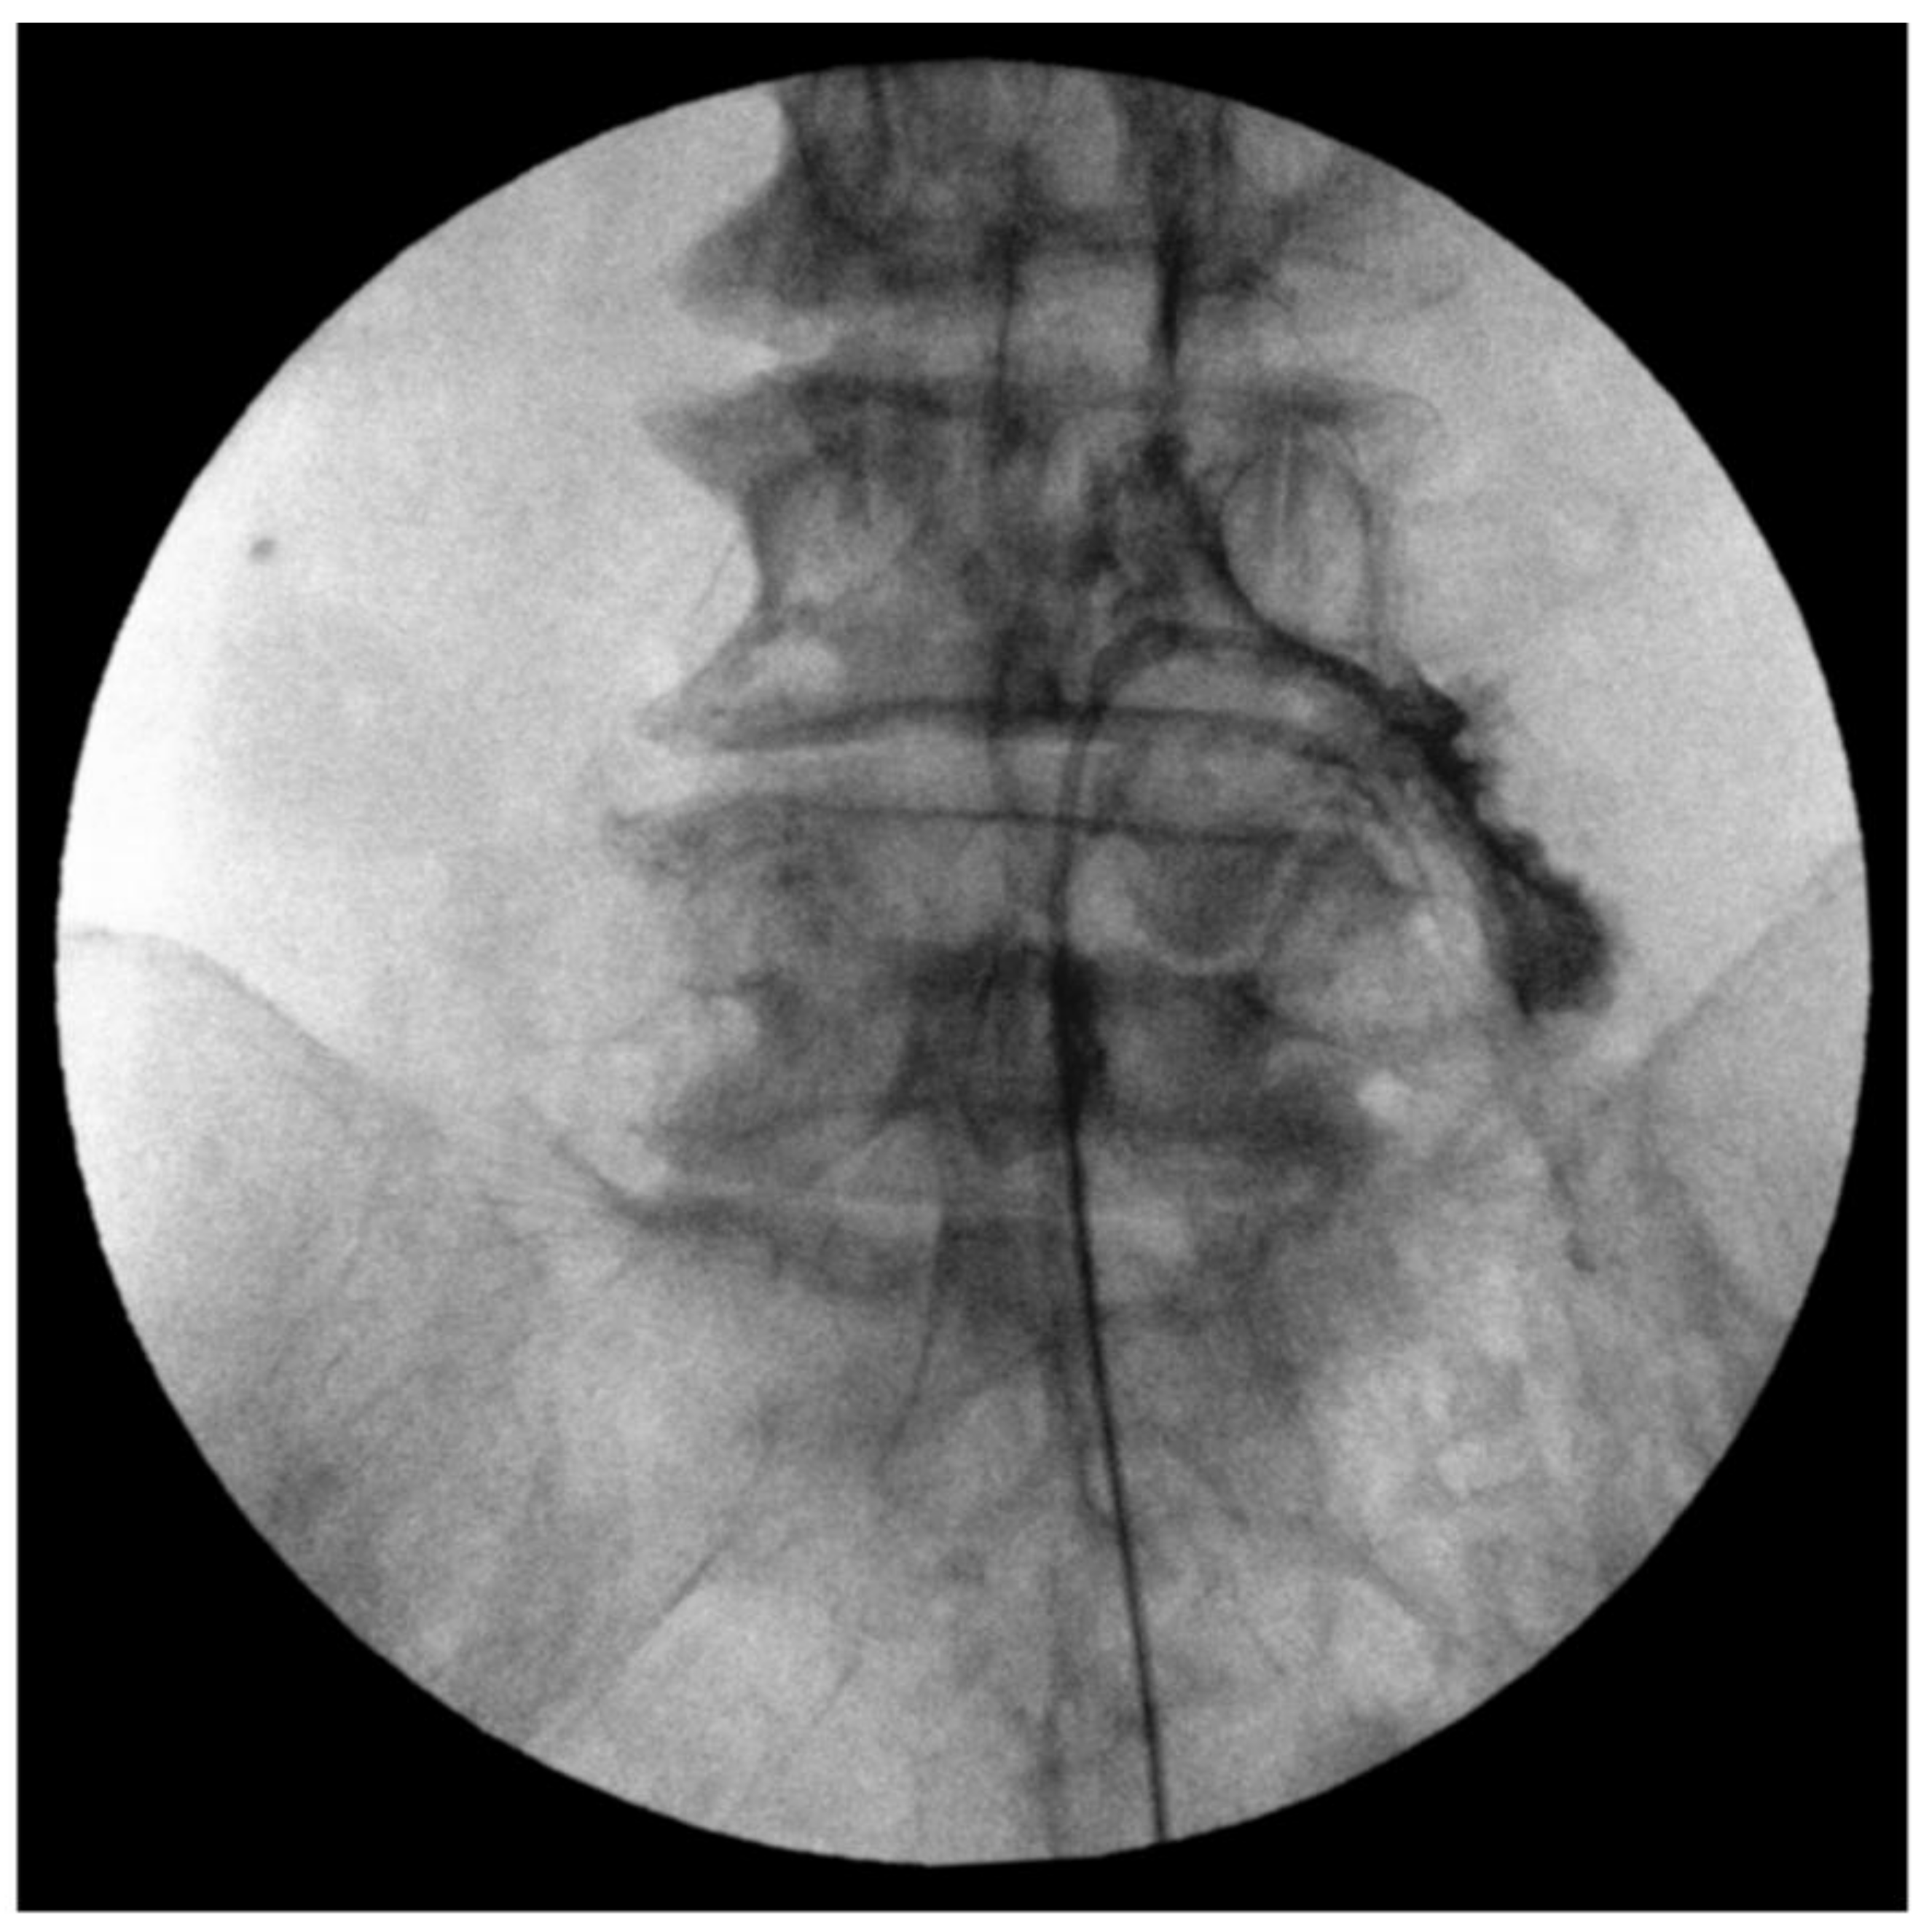

2.3. Fluoroscopy-Guided Lumbar Percutaneous Epidural Adhesiolysis